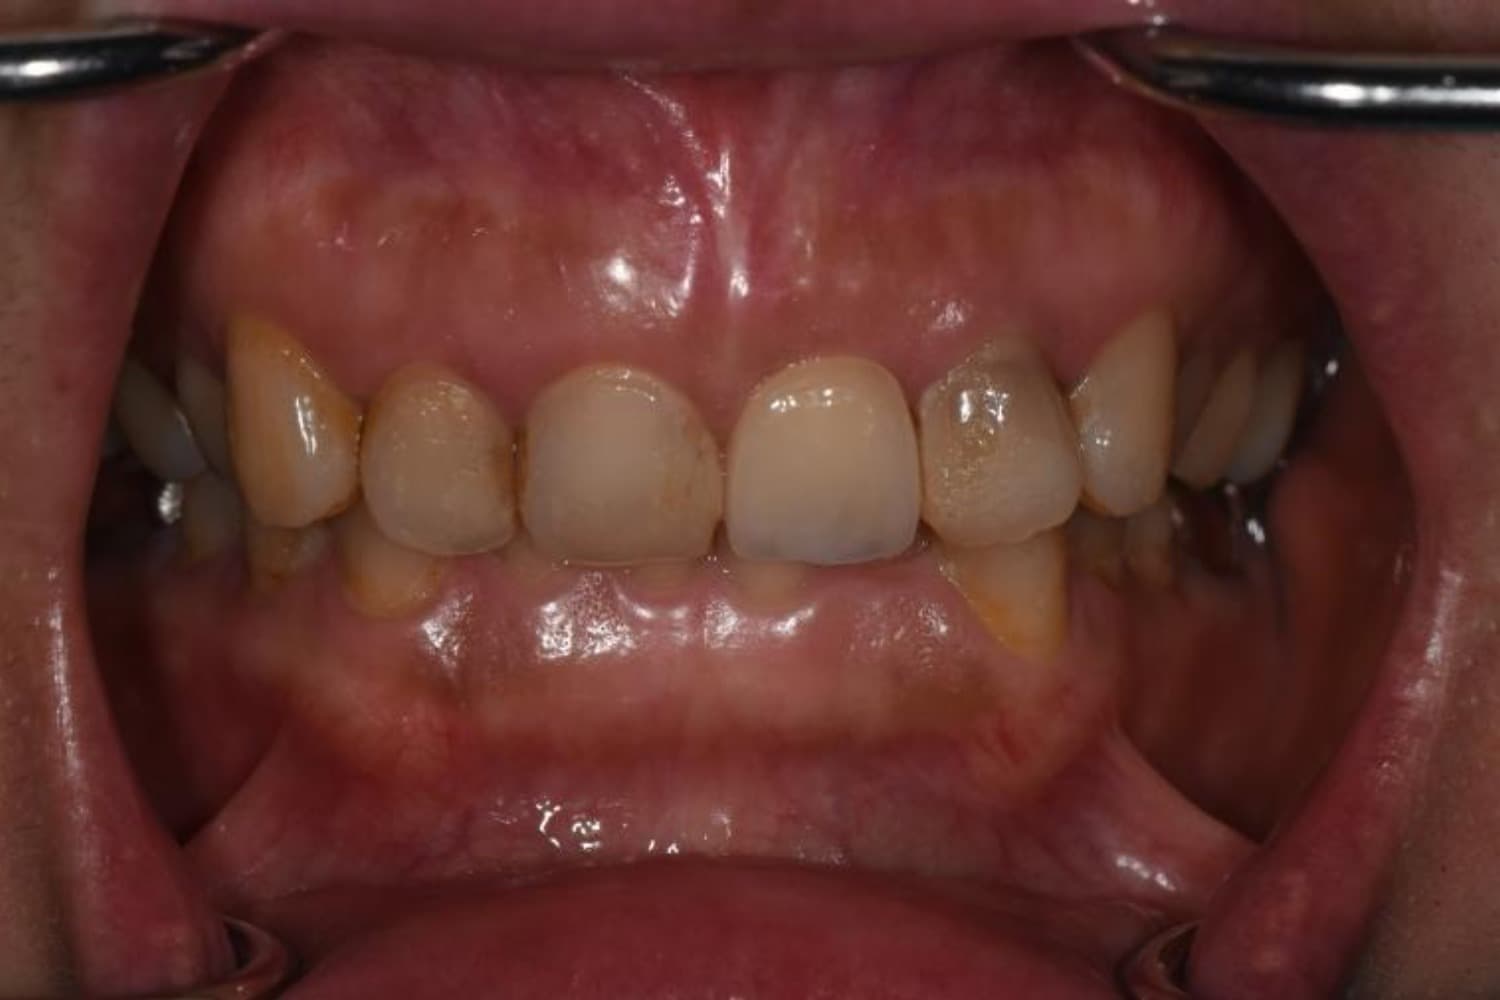

上顎前歯1本欠損症例(1)

Before

After

歯の根が割れていたため抜歯をおこないました。インプラント・ブリッジ・義歯それぞれのメリットやデメリットをお話させていただき、インプラントでの治療を選択されました。

年齢

46歳

性別

女性

主訴

前歯の色味が気になる

治療期間

11ヵ月

費用

60万円

副作用・リスク

インプラント治療は外科的な処置を伴い、多少の腫れや痛みが出ることがあります。 多くの場合は鎮痛薬で和らげることができます。